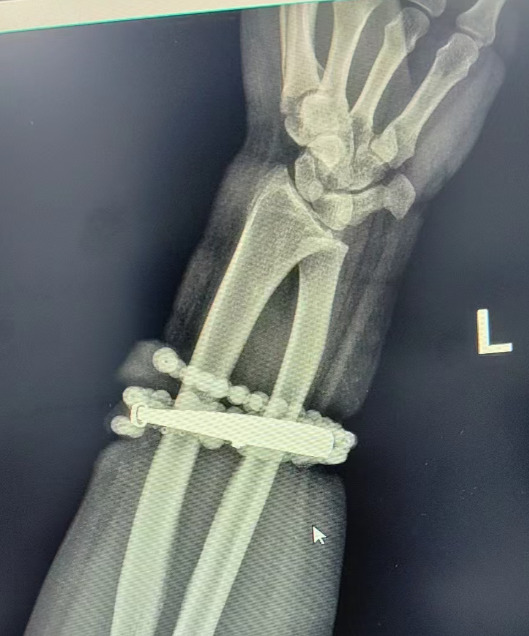

據內地傳媒報道,33歲龔女士戴銀手鐲和串珠近十年,幾乎從未摘下。隨著時間推移,體重有所增加,手腕逐漸被勒得緊繃,但她並未在意。直到近半年,龔女士手腕的皮膚出現反覆瘙癢、發紅,以為是普通皮炎,便自行買藥膏塗抹。然兩周前情況急轉直下,手腕不僅疼痛加劇,還出現明顯紅腫,甚至有膿液滲出,才驚覺手鐲和串珠已經有一部分「長」進了肉內,根本取不下來。

送院檢查後,醫生證實是典型的首飾長期壓迫、摩擦,加上細菌感染,引發慢性炎癥和肉芽組織增生,手鐲和串珠已經成了一個不斷刺激皮膚、污染傷口的「病竈」,如果不盡快手術取出,感染可能進一步擴散,甚至危及生命或影響手臂功能。經過一個多小時手術,醫生將手鐲和串珠從增生組織中完整剝離出來,龔女士事後恢復良好,已順利出院。